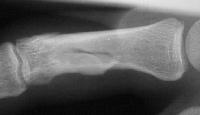

Six months after surgery: